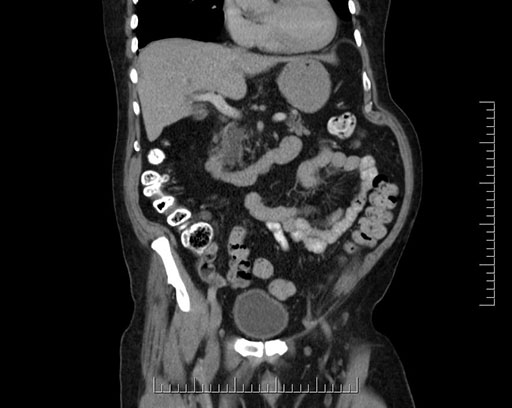

Whipple (pancreaticoduodenectomy) [case 7]

Imaging Analysis

Look through the patient's CT scan to identify any areas of concern for the necessary procedure.

Based on your CT findings, which issue(s) would give reason for "planned slowing down moment(s)" in this case?

Considering a standard Whipple procedure, what step(s) of the operation would you do differently in this case?